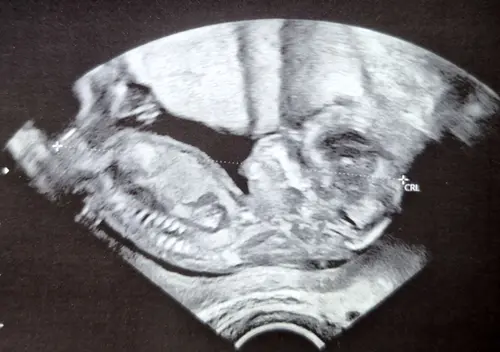

Zie je het hierop?

De nub ligt praktisch in lijn met de ruggengraat, dus ik zou mijn gokje wagen op een meisje. Maar kan ook een vertekend beeld zijn van de echo. Spannend!

Ik heb de uitslag, het is een meisje 馃グ馃┓